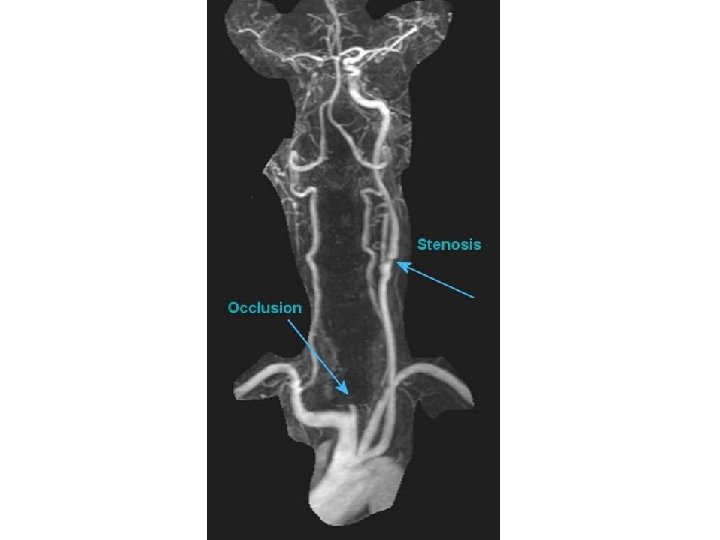

stenosis

Clinical relevance • vertebrobasilar insufficiency • beauty parlour syndrome – vertigo – diplopia, blurred vision – stroke • steal syndrome

Subclavian steal syndrome • clinically significant reduction in blood supply to brain stem and cerebellum • reversal of blood flow through a. vertebralis due to occlusion/ stenosis of central part of AS or TBC • symptoms: vertigo, syncope, intermittent claudication of involved upper limb